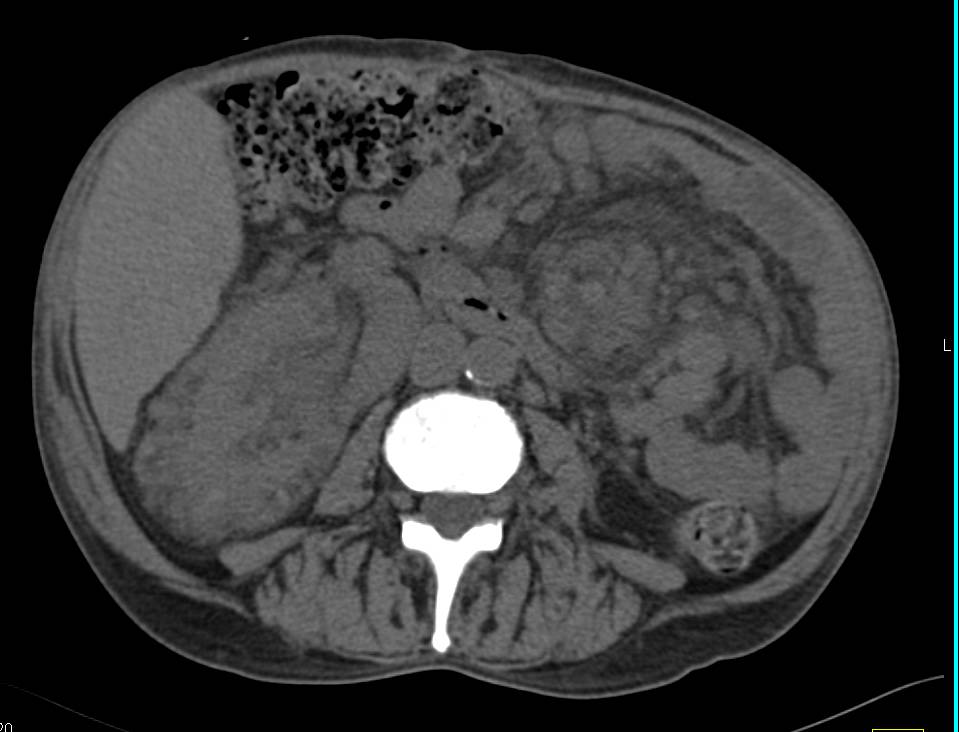

Papillary Renal Cell Carcinoma